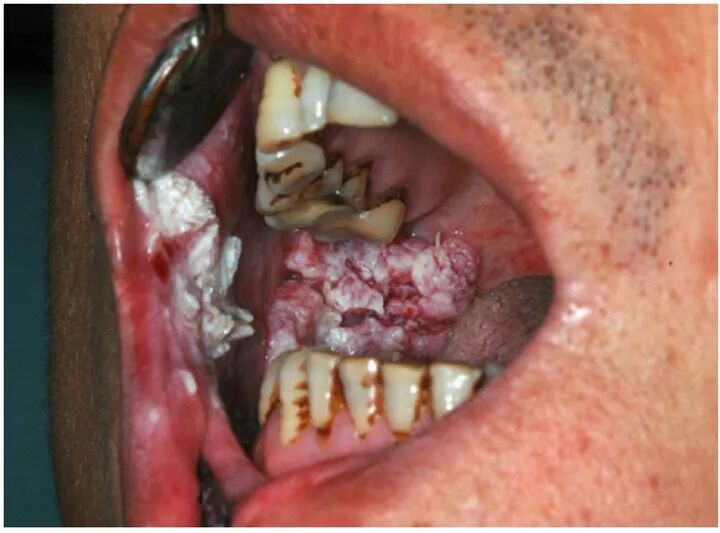

口腔癌患者的口腔黏膜丨参考文献[3]

结合上述槟榔碱的性能,结果可想而知,癌变只是量变引起的质变而已。

嚼槟榔引发的口腔黏膜病变丨参考文献[2]